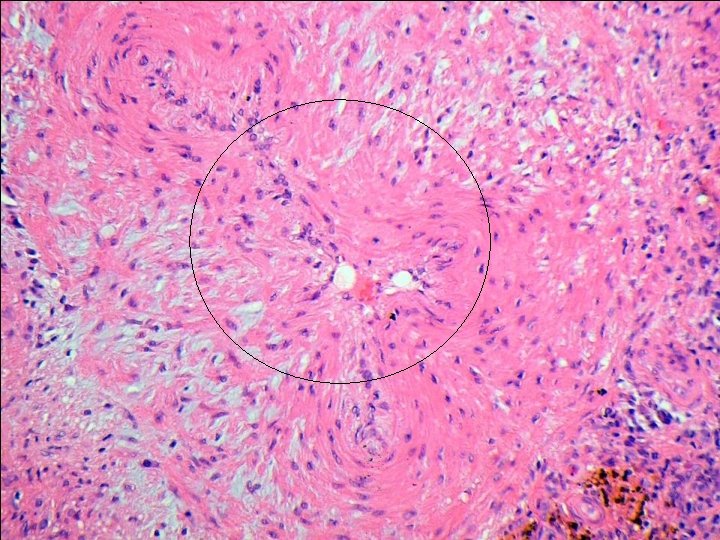

Temporal arteritis Idiopathic, granulomatous vasculitis of large or medium sized elastic arteries. SKIP LESIONS Predilection for superficial temporal artery, but can affect cerebral arteries, carotids, coronary arteries, aorta, renal arteries etc… Pathogenesis-actinically damaged elastic tissue-trigger cell-mediated immune response ? Infection? Histology-with and without giant cells. Adventitial acute and chronic inflammation with involvement of media (muscle layer). Fragmentation of internal elastic lamina. Giant cells at sites of internal elastic lamina rupture (not always). Inflammatory oedema of intima, with stenosis of lumen.